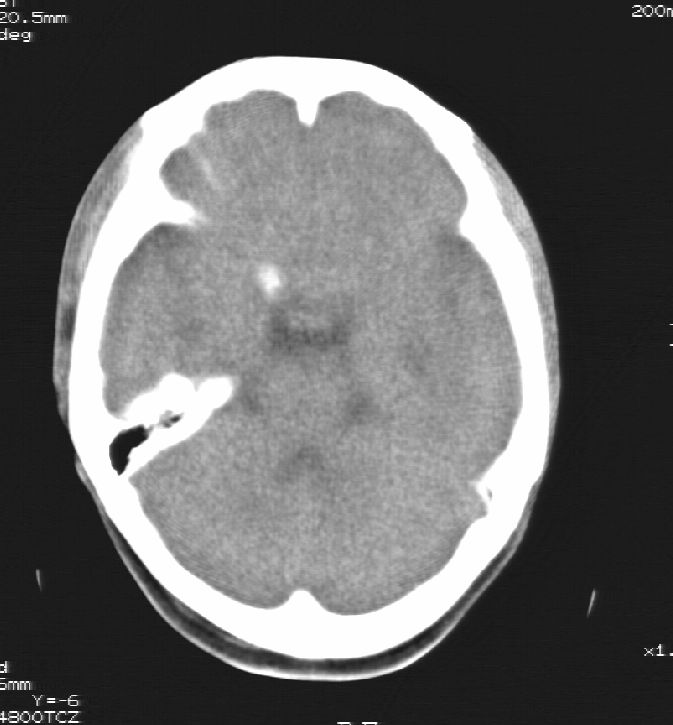

患者男,22岁,因外伤入院,低密度影ct值约-120hu。

胼胝体发育不全合并 透明隔缺如 、脂肪瘤。

胼胝体发育不全合并脂肪瘤;建议必要时行mri检查。

脑水肿,头皮下血肿,胼胝体发育不全、合并脂肪瘤及钙化;建议必要时行mri检查。

畸胎瘤也有可能

胼胝体发育不全、合并脂肪瘤及钙化。